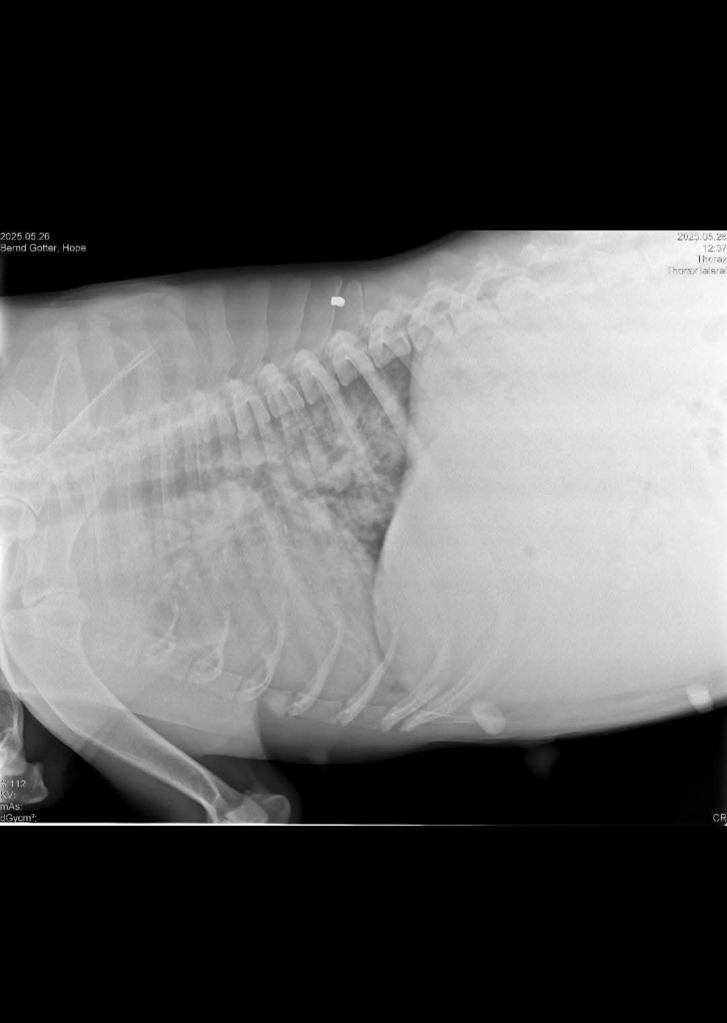

Wir hatten gestern Abend einen Videocall mit Hopes Besitzerin. Am Montag wurde Hopes Lunge geröntgt und ihr Herz wiederholt geschallt. Die ursprünglich geplante Herz OP wurde aufgrund neuer Erkenntnisse abgesagt. Hope hat weiterhin Wasser im Bauch, ihre Lunge arbeitet sehr schlecht, wodurch Hope Schwierigkeiten beim atmen hat. Ihr Zustand ist kritisch, sie ist schwach und bekommt aktuell täglich 7 verschiedene Medikamente. In der Lungenarterie wurden Würmer entdeckt. Eine Entfernung der Würmer an dieser Stelle ist nicht möglich, da Hope verbluten würde. Für eine Narkose ist die Hündin derzeit nicht stabil genug und würde sie nicht überleben. Die rechte Herzkammer ist beschädigt und die Herzpumpe in ihrer Funktion auch sehr beeinträchtigt. Alles in allem sind die Gegebenheiten wirklich schwer, also gibt es zum jetzigen Stand nur die Möglichkeit rein medikamentös zu behandeln und die Würmer abzutöten. Eine OP ist nicht auszuschließen, sofern Hope stabil genug sein wird, doch das braucht Zeit und viel Glück. In der Hoffnung, dass die Medikamente ihr bestes tun, werden Hopes Herz und Lunge kommende Woche Mittwoch nochmal geröntgt und geschallt.

Leider wurden durch die Röntgenaufnahmen auch 2 Diabolos entdeckt, wovon eine an ihrer Rippe befindlich ist. Schlimm genug, dass Hope so schlecht behandelt und misshandelt wurde. Man hat auch noch auf sie geschossen! Die andere Patrone sitzt sehr ungünstig in der Nähe der Wirbelsäule und muss ggf. entfernt werden, was aber auch gewisse Risiken mit sich bringt!